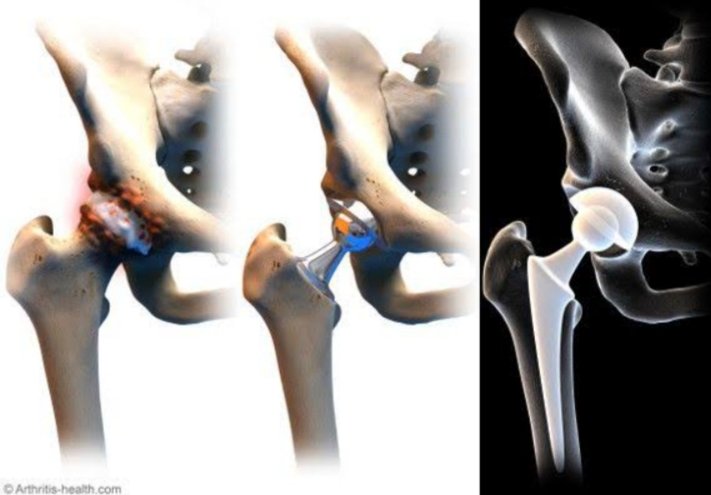

HIP SURGERY

Hip fractures, Hip replacement, Hip arthoscopy